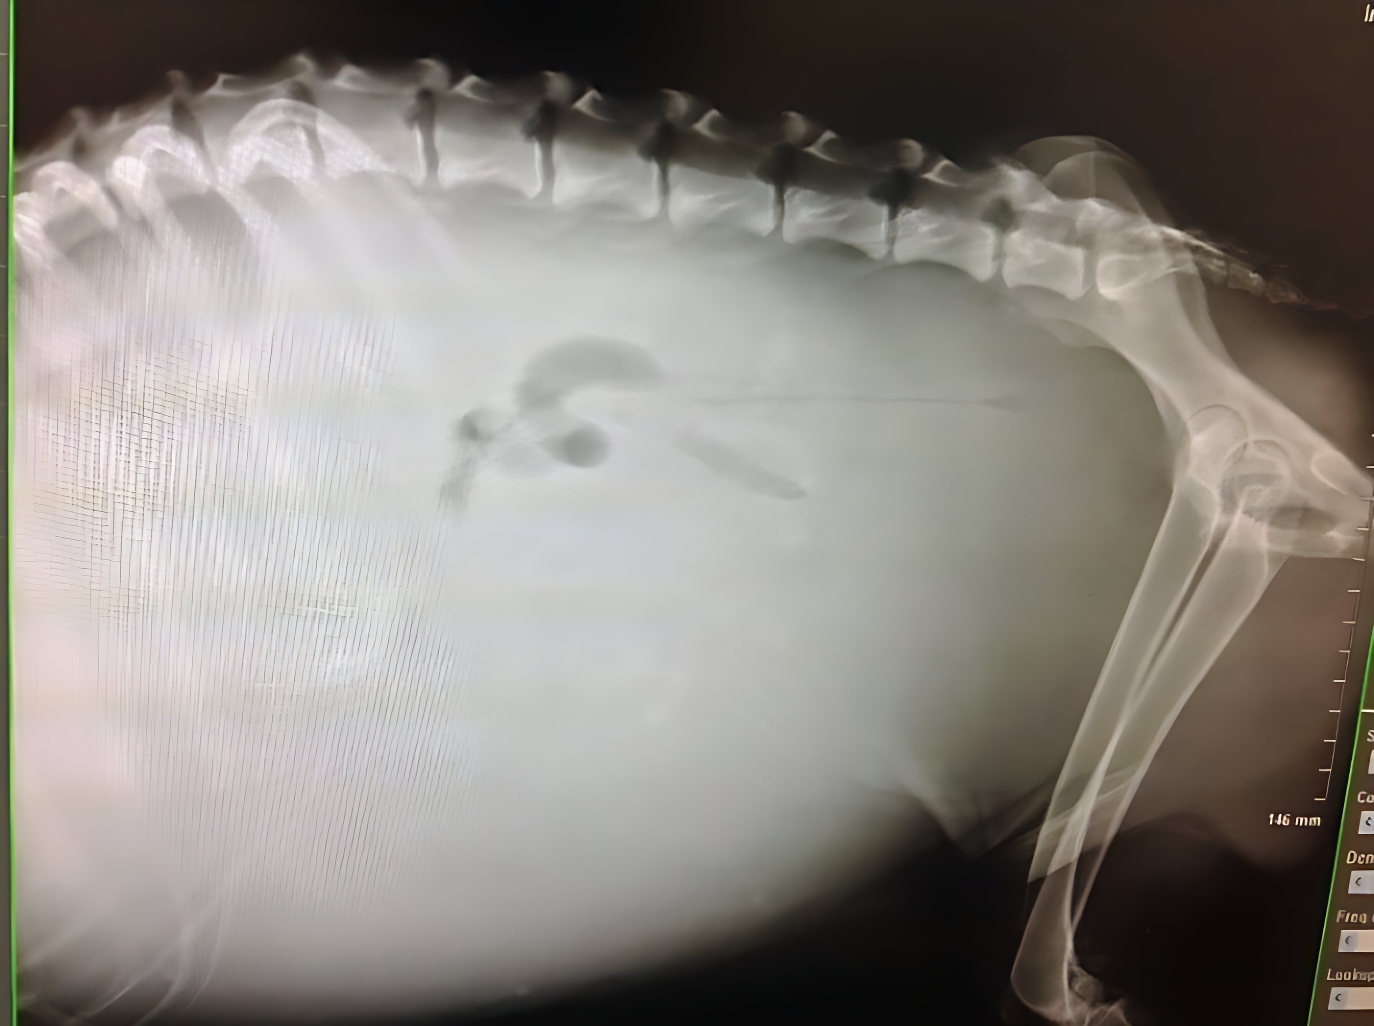

毛寶貝心臟疾病常見於中老年齡,如飼養品種小型犬如吉娃娃、馬爾濟斯、博美犬等容易發生心臟瓣膜問題,貓咪也有肥厚型心肌病,甚至會產生血栓導致四肢冰冷及癱瘓問題,另外台灣地處亞熱帶地區,由蚊蟲傳播心絲蟲感也很常見。心臟問題如未及早發現,往往等到出現咳嗽、呼吸急促、鼻孔出現粉紅色泡沫,甚至突然昏厥時,病情已相當嚴重。淡水動物之家日前即有救援一隻中型米克斯犬,腹部莫名腫大,脹大的肚皮拍打像水球有水波感,經過淡水動物之家獸醫師黃仲煜診療後確定為心絲蟲感染導致鬱血性心衰竭,經過腹腔穿刺引流後由抽出2公升的腹水。